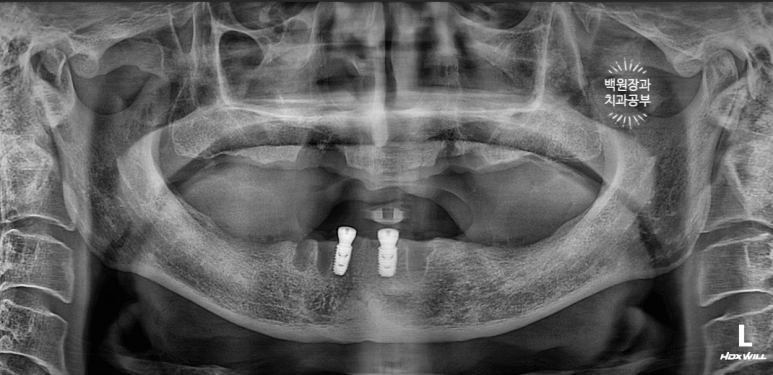

노란 점선이 보이시나요? 잇몸뼈의 높이입니다.

상당한 양의 임플란트 주변 뼈가 녹아서 없어져 버린것을 보실 수 있어요.

수술 후 찍은 치과용 파노라마 엑스레이를 보시면,

임플란트가 사라진 자리에 충분히 자리잡은 뼈이식재를 보실 수 있을거에요!

치아를 뽑는 발치던 임플란트를 제거하는 임플란트 제거술이던,

뼈이식을 하게되면 약 4개월 정도의 치유기간이 필요합니다.